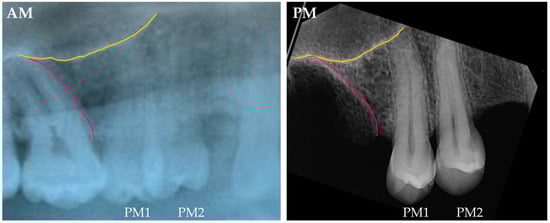

The comparison between antemortem panoramic radiographs and postmortem periapical radiographs is commonly performed in cases utilizing the maxillary sinus. In these cases, only the lower part of the maxillary sinuses can be compared (Figure 2).

Figure 2. Comparison between an antemortem panoramic radiograph fragment (AM) and postmortem periapical radiograph (PM) of the right maxillary premolar and molar area. The inferior border (or the floor) of the maxillary sinus is highlighted in yellow, and the 1st and 2nd premolars are labeled as PM1 and PM2, and the mesial alveolar portion of the molar is highlighted in pink. This comparison depicts consistent morphologies between the AM and PM radiographs, where the relationship of the inferior part of the maxillary sinus with the dental roots is key for the comparison. Source: Department of Applied Forensic Sciences at Mercyhurst University casework.